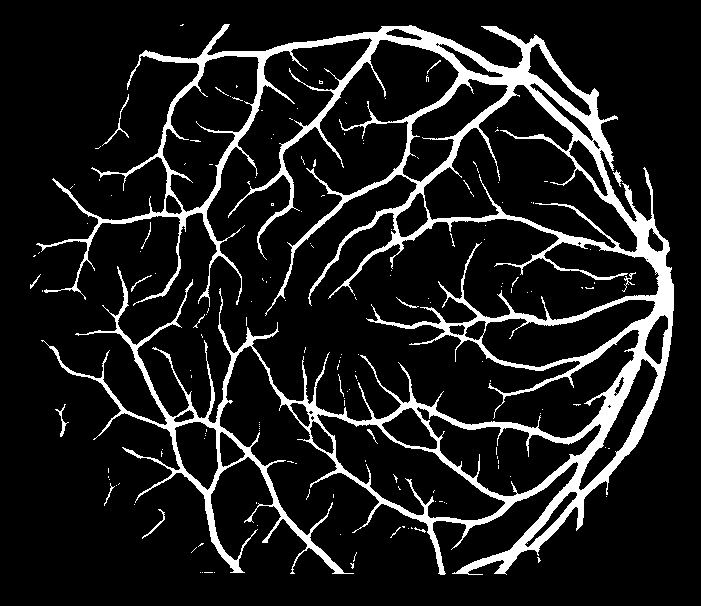

Refer to caption

(a) Ground truth binary mask

(b) Thick vessels binary mask

(c) Thin vessels binary mask

Figure 4: Segregation of ground truth of sample DRIVE image.

After Level-I balancing, the network model is still biased towards the prediction of thick vessel pixels, leaving many thin vessel pixels unidentified. This is because the number of thick vessel’s pixels exceeds those of thin vessel’s pixels. Thus, there is a need to create a balance between the distribution of thick and thin vessel pixels in the training set, termed intra-class balancing. This can be considered another level of balancing on top of Level-I balancing, hence the term Level-II balancing. The balancing obtained from Level-I is further refined by giving an equivalent representation to thick vessel pixels and thin vessel pixels in the training set. The categorization of thick and thin vessel patches requires the segregation of ground truth binary images based on thick and thin vessel pixels. The thick vessels pixels mask is acquired through morphological opening [44] operation, while the thin vessels pixels mask is obtained by subtracting the thick vessel mask from the original ground truth mask. Figure 4 shows the ground truth image of a sample DRIVE image along with the corresponding thick and thin vessel mask images.